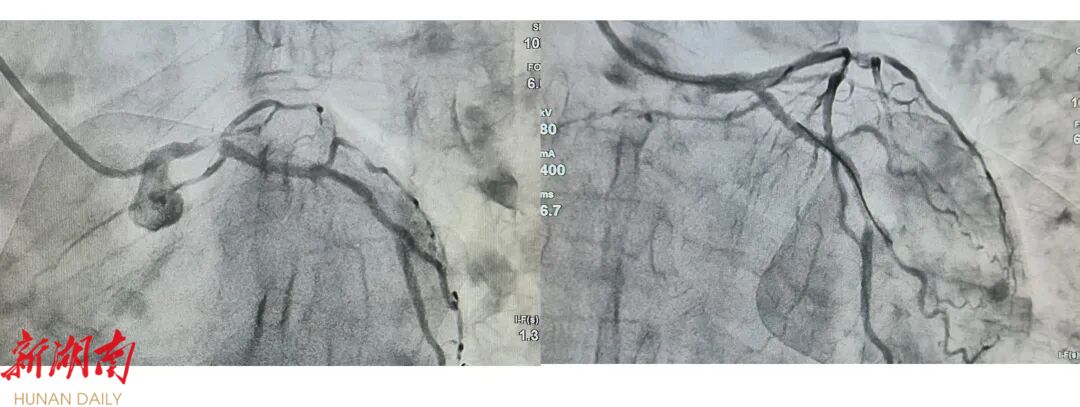

患者“急性广泛前壁心肌梗死”,术前、术后对比

当日下午13:29,通过无缝衔接的绿色通道,患者被直接送入导管室,急诊 随即展开。术中情况极为复杂凶险:造影提示左主干尾部中度狭窄伴血栓形成,前降支开口急性闭塞,回旋支开口血栓,右冠脉近中段弥漫性重度狭窄。这属于最为棘手的多支血管病变型急性心肌梗死。手术过程中,患者更突发血压骤降、心率减慢,生命体征一度濒临崩溃。 面对极端复杂的冠脉解剖结构与术中循环衰竭的险情,县人民医院心内科介入团队沉着冷静,迅速实施升压、扩容等循环支持,同时精准操控导丝、球囊等介入器械,在纷繁的病变血管中成功开通罪犯血管。造影评估、球囊扩张、支架植入......一系列操作在紧张而有序的氛围中精准推进。

13:54,随着支架成功释放,堵塞血管恢复前向血流,患者胸痛症状即刻缓解,血压与心率逐渐趋于稳定。导管室内所有人员紧绷的神经终于得以稍缓,这场与时间赛跑、同死神博弈的抢救取得了关键胜利。